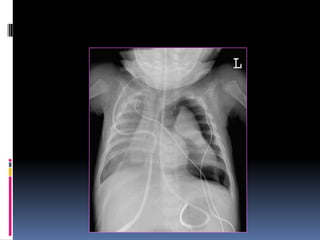

CXR - PA Vs AP view.

PA- the x-rays penetrate through the back of the

patient on to the film

AP-the x-rays penetrate through the front of the

patient on to the film.

CXR - PAVs AP view. PA- the x-rays penetrate through the back of the patient on to the film AP-the x-rays penetrate through the front of the patient on to the film.